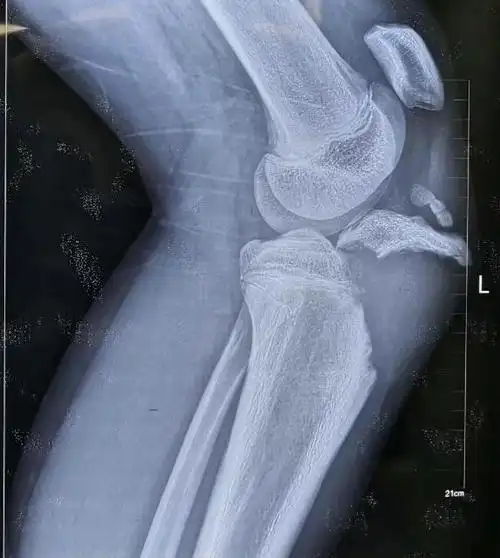

特殊胫骨结节撕脱性骨折手术分享